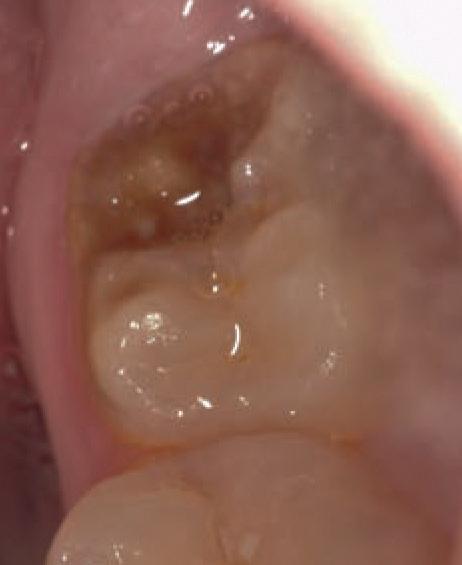

Figure 4. Maxillofacial surgery. Figure 6. TMJ analysis. Figure 8. Airway analysis. Figure 10. Periodontics. Figure 5. Orthodontics. Figure 7. Implant placement. Figure 9. Prosthodontics. Figure 11. Endodontics.